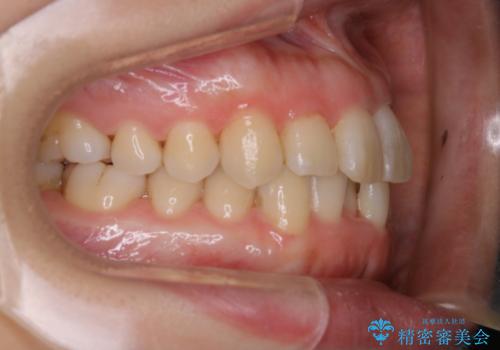

インビザライン・ライトでの抜歯矯正治療 (スリーインサイザー仕上げ)

- 上下の前歯のがたつきが気になるとのことで来院されました。最短治療とインビザラインでの矯正治療をご希望されました。

前歯のがたつきを無くすためには、スペースを確保する必要があります。上の前歯のがたつきは軽度ながたつきのため、歯と歯の間を研磨をして、そのスペースを使い並べていきます。下の前歯は、1本前歯を抜いて研磨せずに、その抜歯したスペースを使い並べることになりました。

下の前歯は、スリーインサイザー仕上げと言って、通常前歯は4本ありますが(犬歯はいれていない)、そのどれか1本を抜歯して前歯を3本にして矯正治療を行うことを言います。また、先天的に歯の本数が少ない方もいますので、矯正治療を行っていなくても元々スリーインサイザーの方もいます。